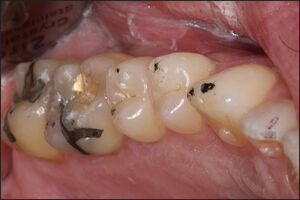

The teeth were dried on 1 side of the arch (operator’s selection), after which each subject closed into their Maximum Intercuspal Position (MIP) with 21 micron-thick articulating paper (Accufilm, Parkell, Inc. Farmingdale, NY, USA) interposed between their teeth, and to then move their mandible into a right excursion out to edges of their right canine teeth, then slide back into MIP, and then move out to edges of their left canine teeth. With this movement the teeth made excursive track lines that marked the long Disclusion Time contacts on the frictionally involved teeth for adjustment (Figure 5).

The pre-ICAGD T-Scan/BioEMG recordings guided the author to the proper areas of the occlusal surfaces that required excursive adjustments. All working and non-working posterior lateral interferences that represented the prolonged frictional contacts were removed completely, while the centric stop contacts were left intact except to lessen their broad surface area into small surface area contacts, located on supporting cusps and in central fossae. This process was repeated on the initial side of treatment until complete visual disclusion had been obtained (Figure 6). The same process of marking the teeth excursively and removing all working and non-working posterior lateral interferences was then performed on the 2nd side of the arch, until complete visual disclusion had been obtained on the 2nd side.